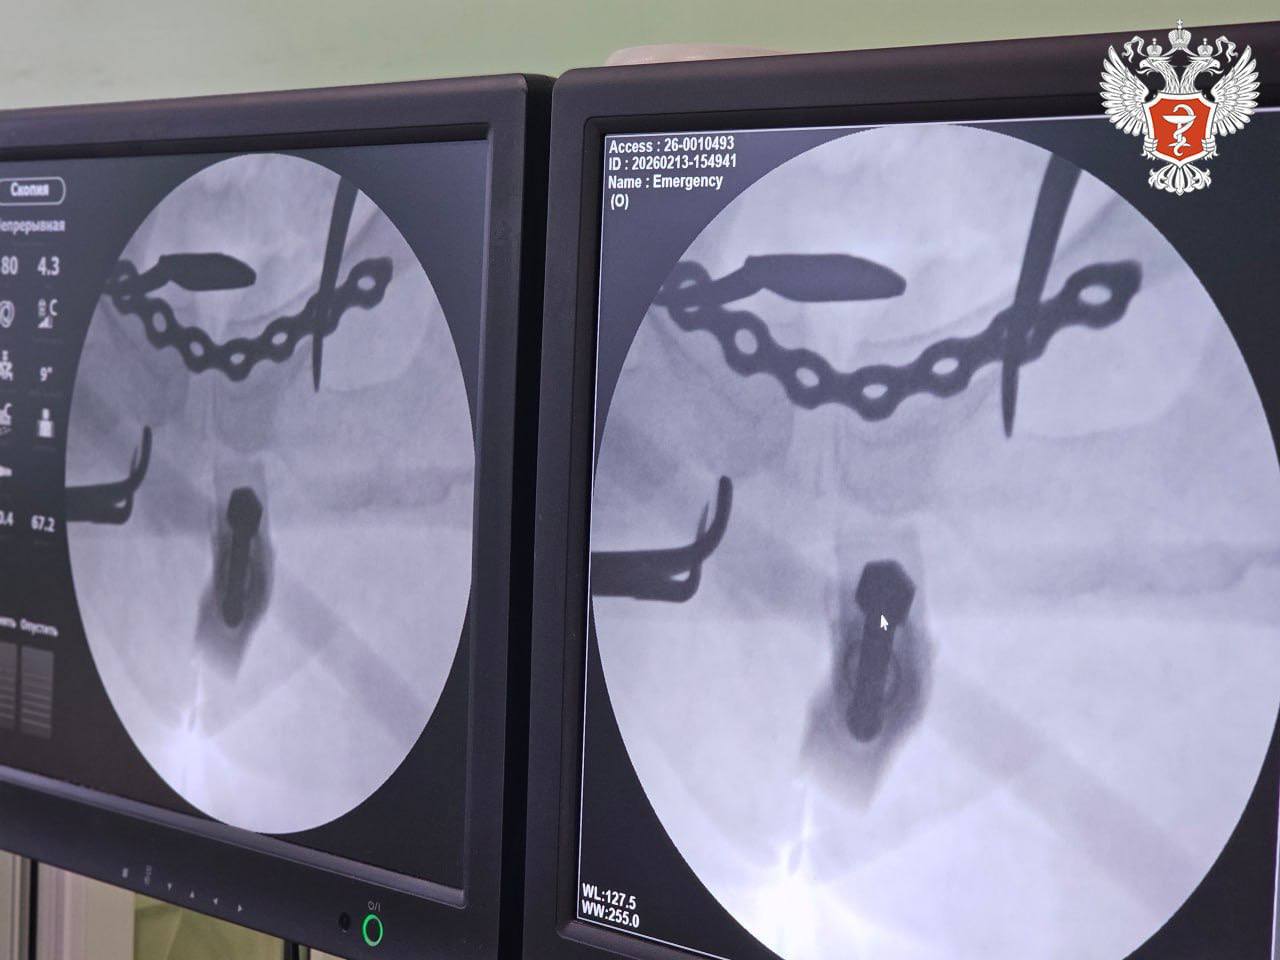

Медики диагностировали крайне тяжелые повреждения таза: двусторонний перелом боковых масс крестца и разрыв лонного сочленения.

Лечение проводилось с применением аппарата внешней фиксации переломов, который позволяет быстро и малоинвазивно стабилизировать состояние пациента.

1 На первом этапе, сразу после поступления, дежурная бригада в рамках противошоковых мероприятий выполнила закрытую репозицию костей таза и их фиксацию внешним аппаратом.

Операция заняла около 20 минут и была выполнена всего через два прокола кожи, что позволило стабилизировать состояние пациентки. Вскоре женщину перевели из реанимации в профильное отделение.

2 На втором этапе врачи зафиксировали переломы: крестец укрепили канюлированными винтами через минимальные проколы, а разрыв лонного сочленения — титановой пластиной через мини-доступ.